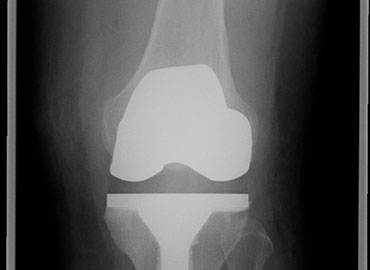

Before and After

Image Gallery

What is a knee replacement?

A knee replacement involves removing the worn joint surfaces from the top end of the shin bone and the bottom end of the thigh bone and sometimes the under surface of the knee cap. Metal and plastic components are cemented into the bone to fill the gap.